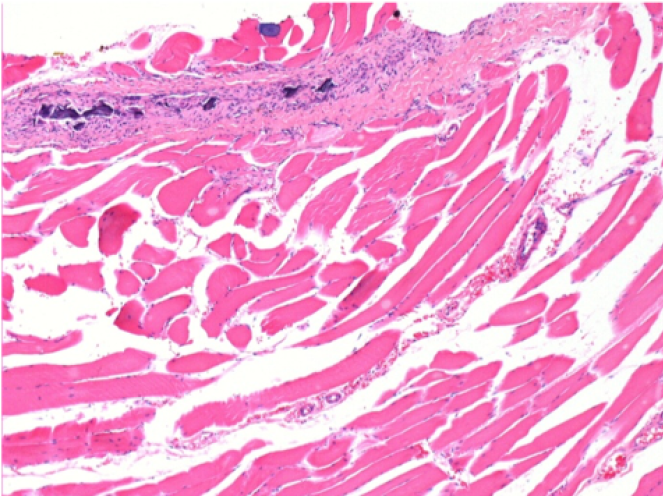

Через 10 днів після ін'єкції Ендопіл 0,1 мл в правий претибіальний м'яз.

Тут можна побачити утворення вакуолей, які оточені лімфоцитами. Вакуолі відрізняються від некрозу тканини. Присутність лімфоцитів пов'язана з проникністю клітинних мембран.